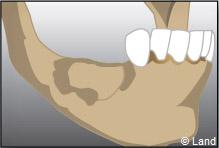

Après 6 mois de cicatrisation, il est possible de poser les implants qui recevront dans un deuxième temps les couronnes.